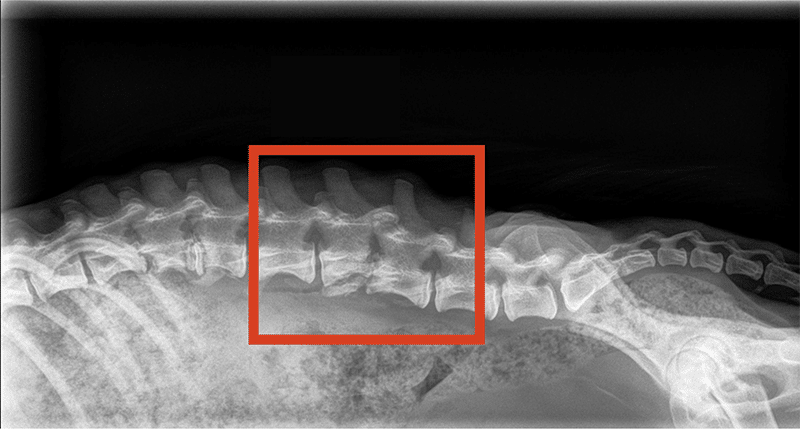

An x-ray shows where an infection caused by migrating foxtails has caused fractures in two of Star’s vertebrae.

Star’s X-rays revealed that one of these foxtails had migrated near her lower spine. She was diagnosed with a painful condition called Discospondylitis, which occurs when an infection affects both the bones of the spine and the tissue between them. In Star’s case, the infection was severe enough that it caused fractures in two of her vertebrae. Swelling was also pushing on Star’s spinal cord, causing pain and nerve disruption that made it difficult for her to walk.